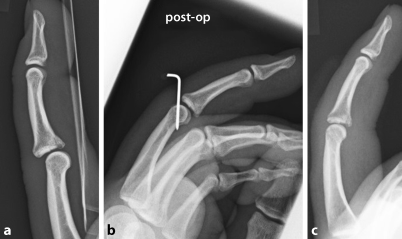

Traumrad Hand und Handgelenk | OrthoRad

Traumrad Hand und Handgelenk | OrthoRad from www.idr.med.uni-erlangen.de